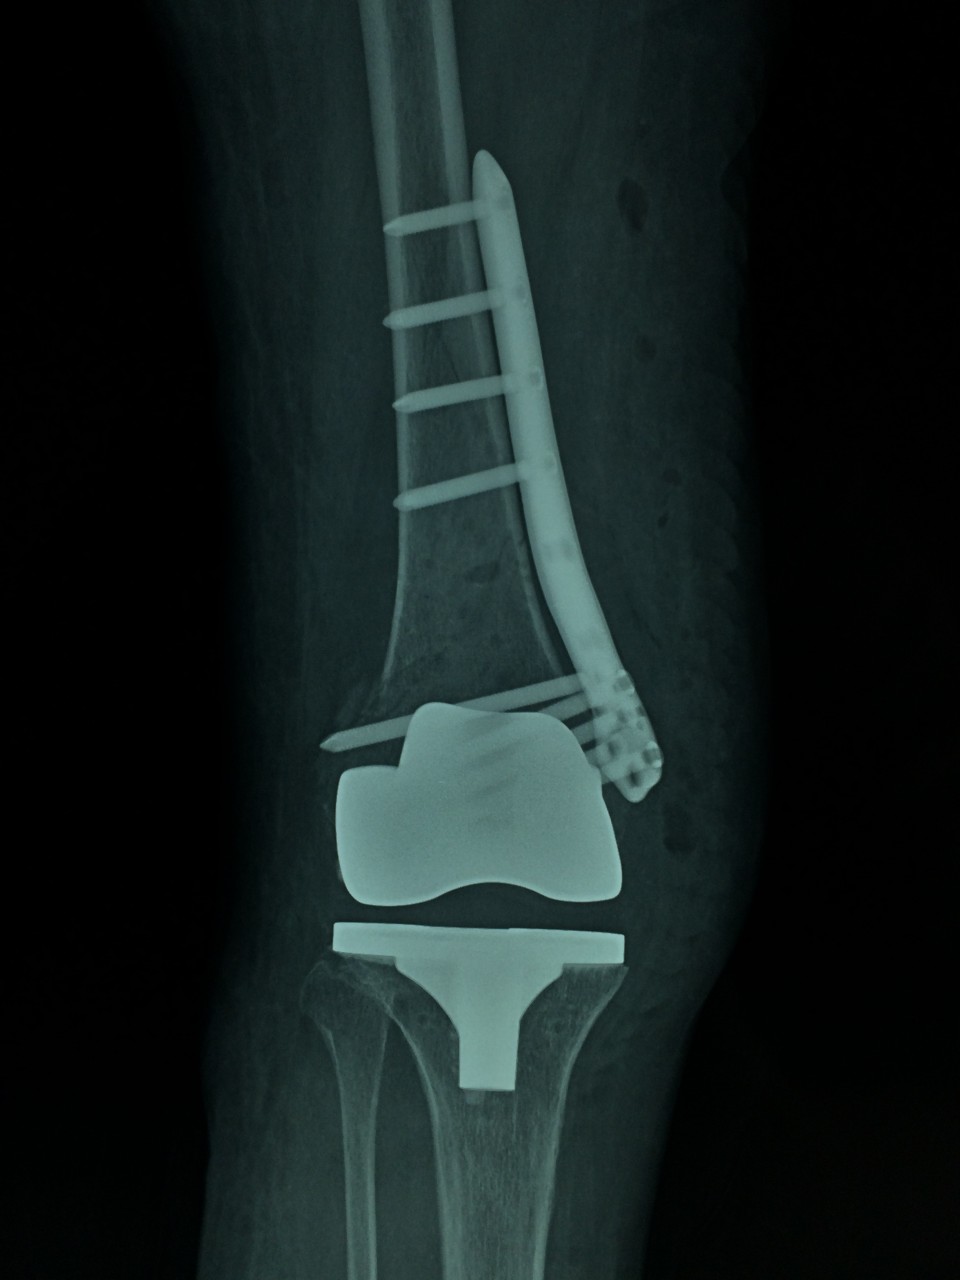

近日,我院关节中心成功完成一例重症类风关合并股骨远端骨折患者的关节置换手术。该患者长期服用激素及免疫抑制剂,骨质疏松较重;受伤前膝关节无法伸直,屈曲畸形,膝关节活动度仅15°;骨折的部位位于股骨远端,骨折处理不当,会直接影响假体的安置,造成手术的失败,因此手术难度非常大,对手术程序及逻辑性的严密度要求高。针对患者的复杂病情及手术难点,关节中心胡勇教授在风湿科、麻醉科的大力配合下,一期完成了骨折固定及人工表面全膝关节置换术。术后患者下肢力线恢复良好,骨折解剖复位,关节恢复过伸,术后5天,关节屈伸活动度恢复致40°。该手术的完成,标志着我院关节中心在复杂性关节病的治疗上又迈出了坚实的一步。